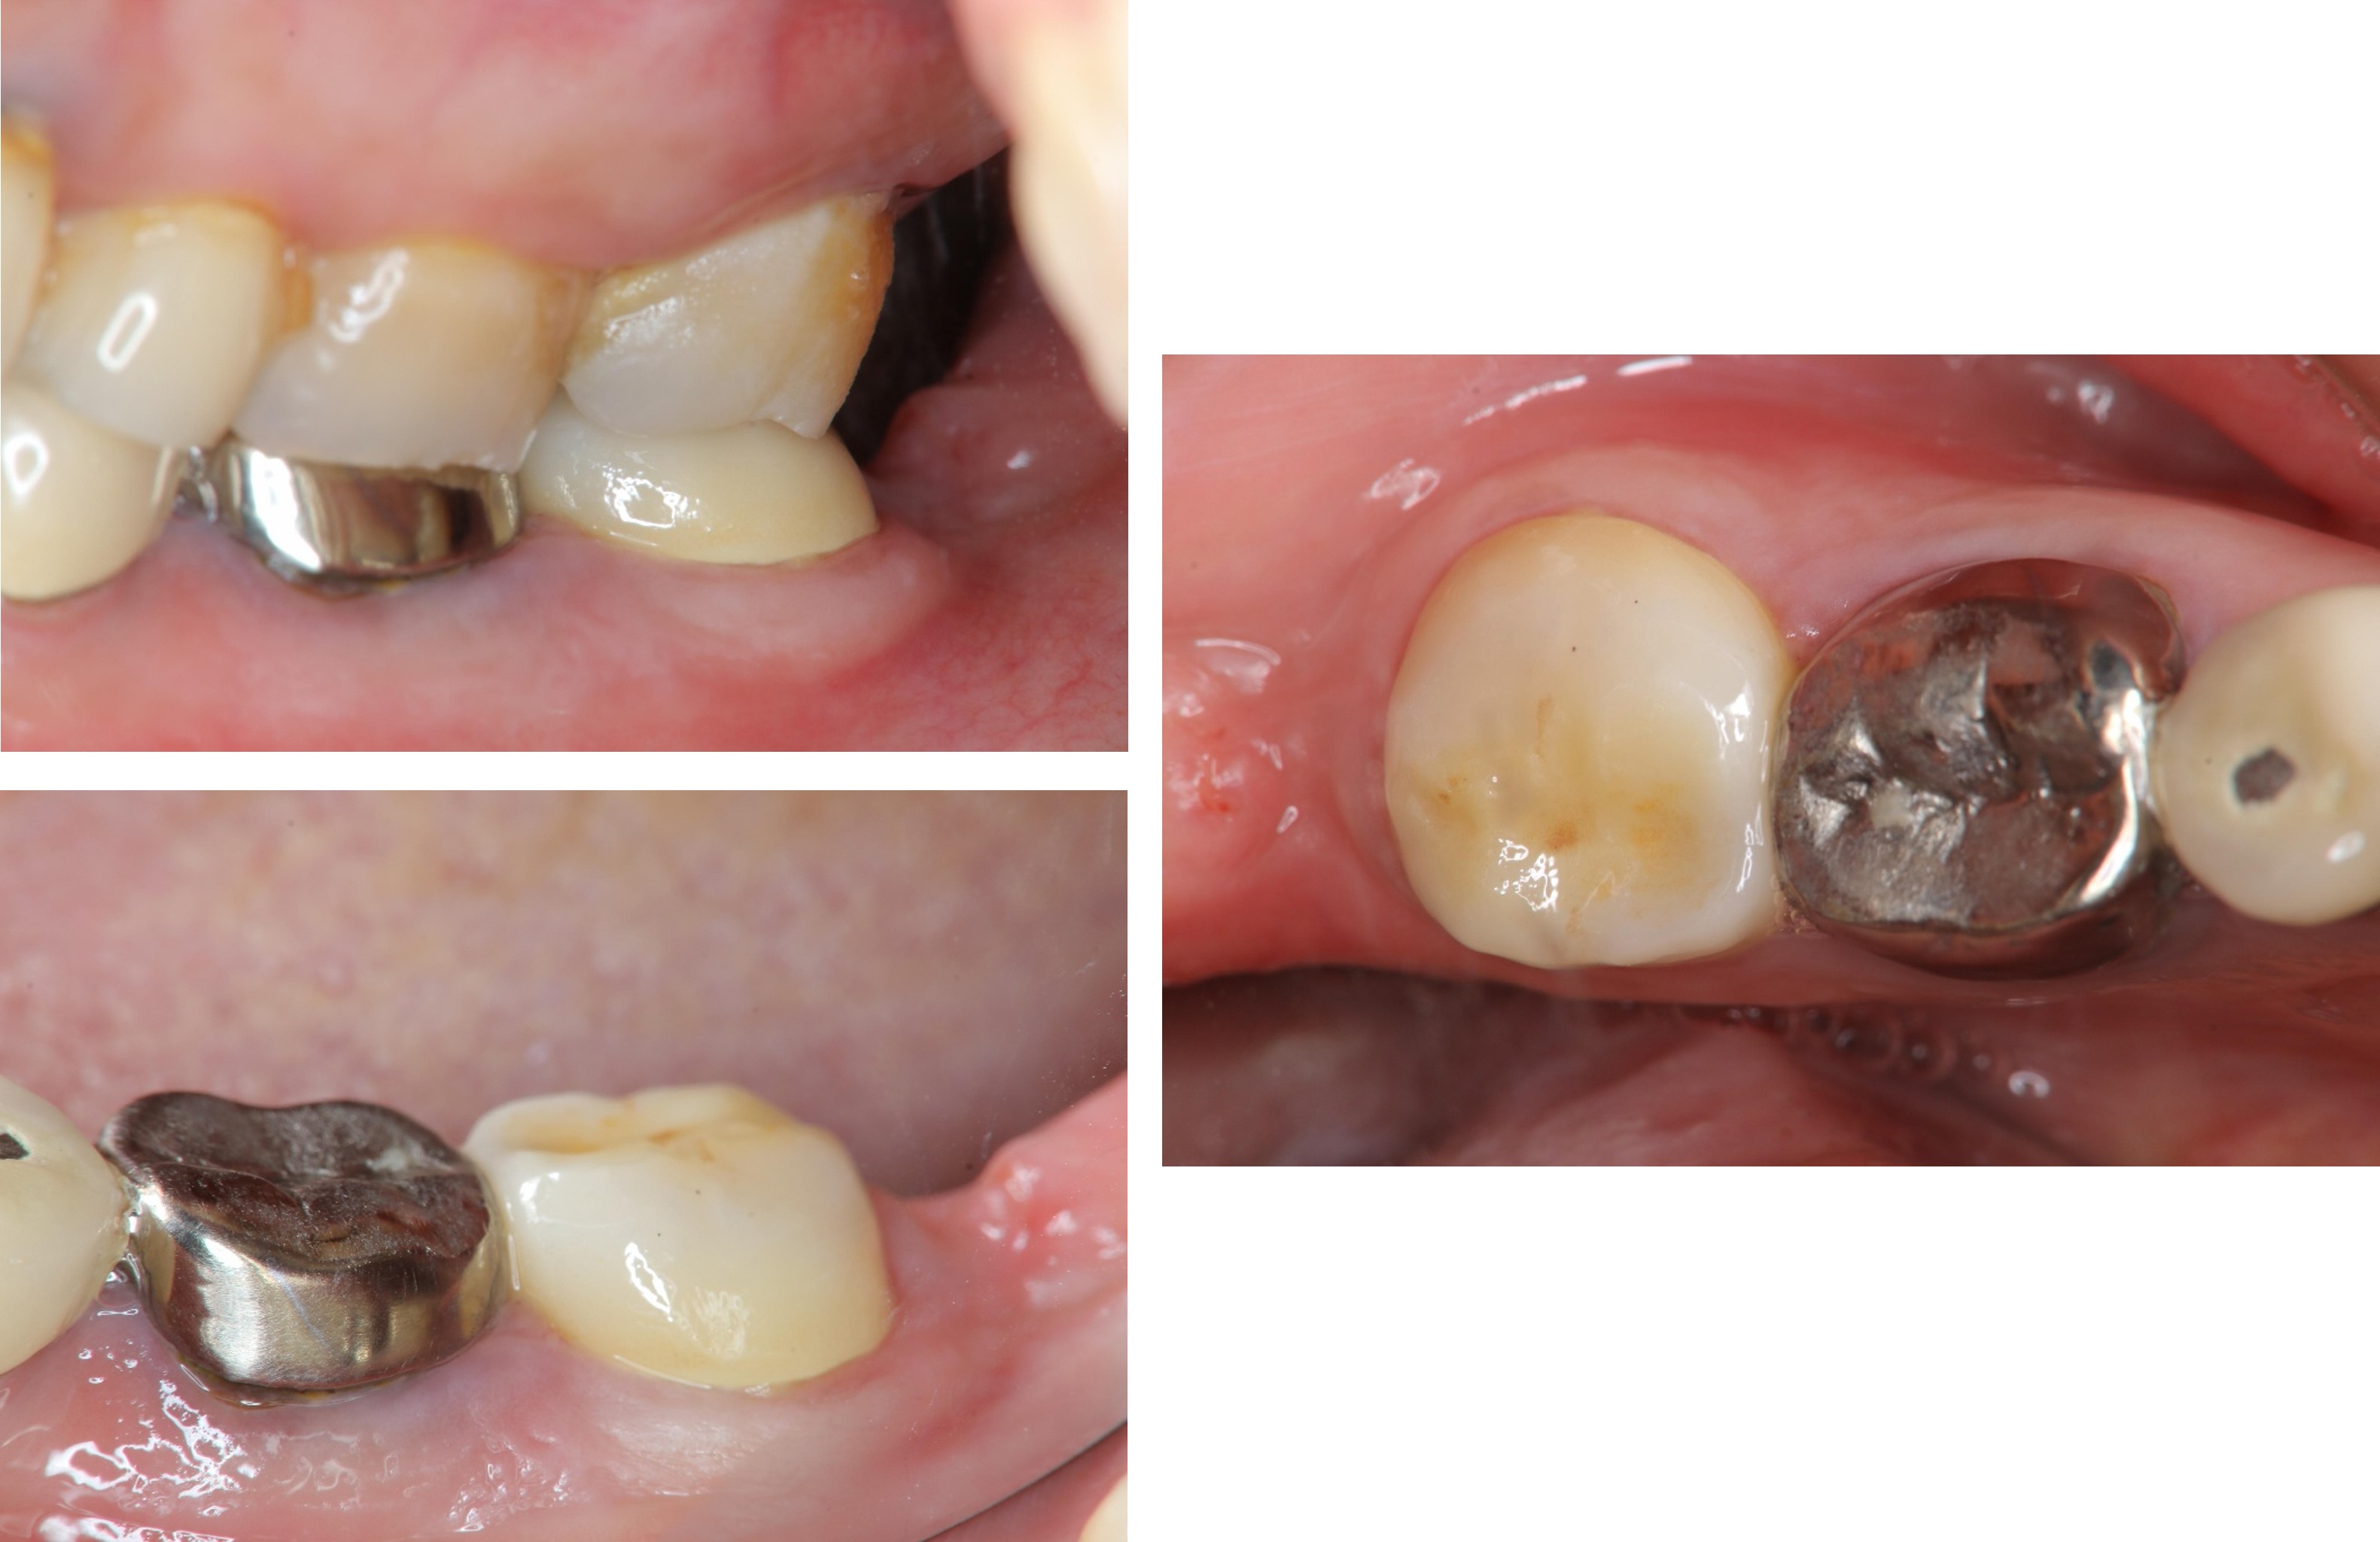

膺復前評估牙齦、牙齒狀態

照相比色

治療後,牙周咬合良好

治療後,密合度良好

術前、術後比較